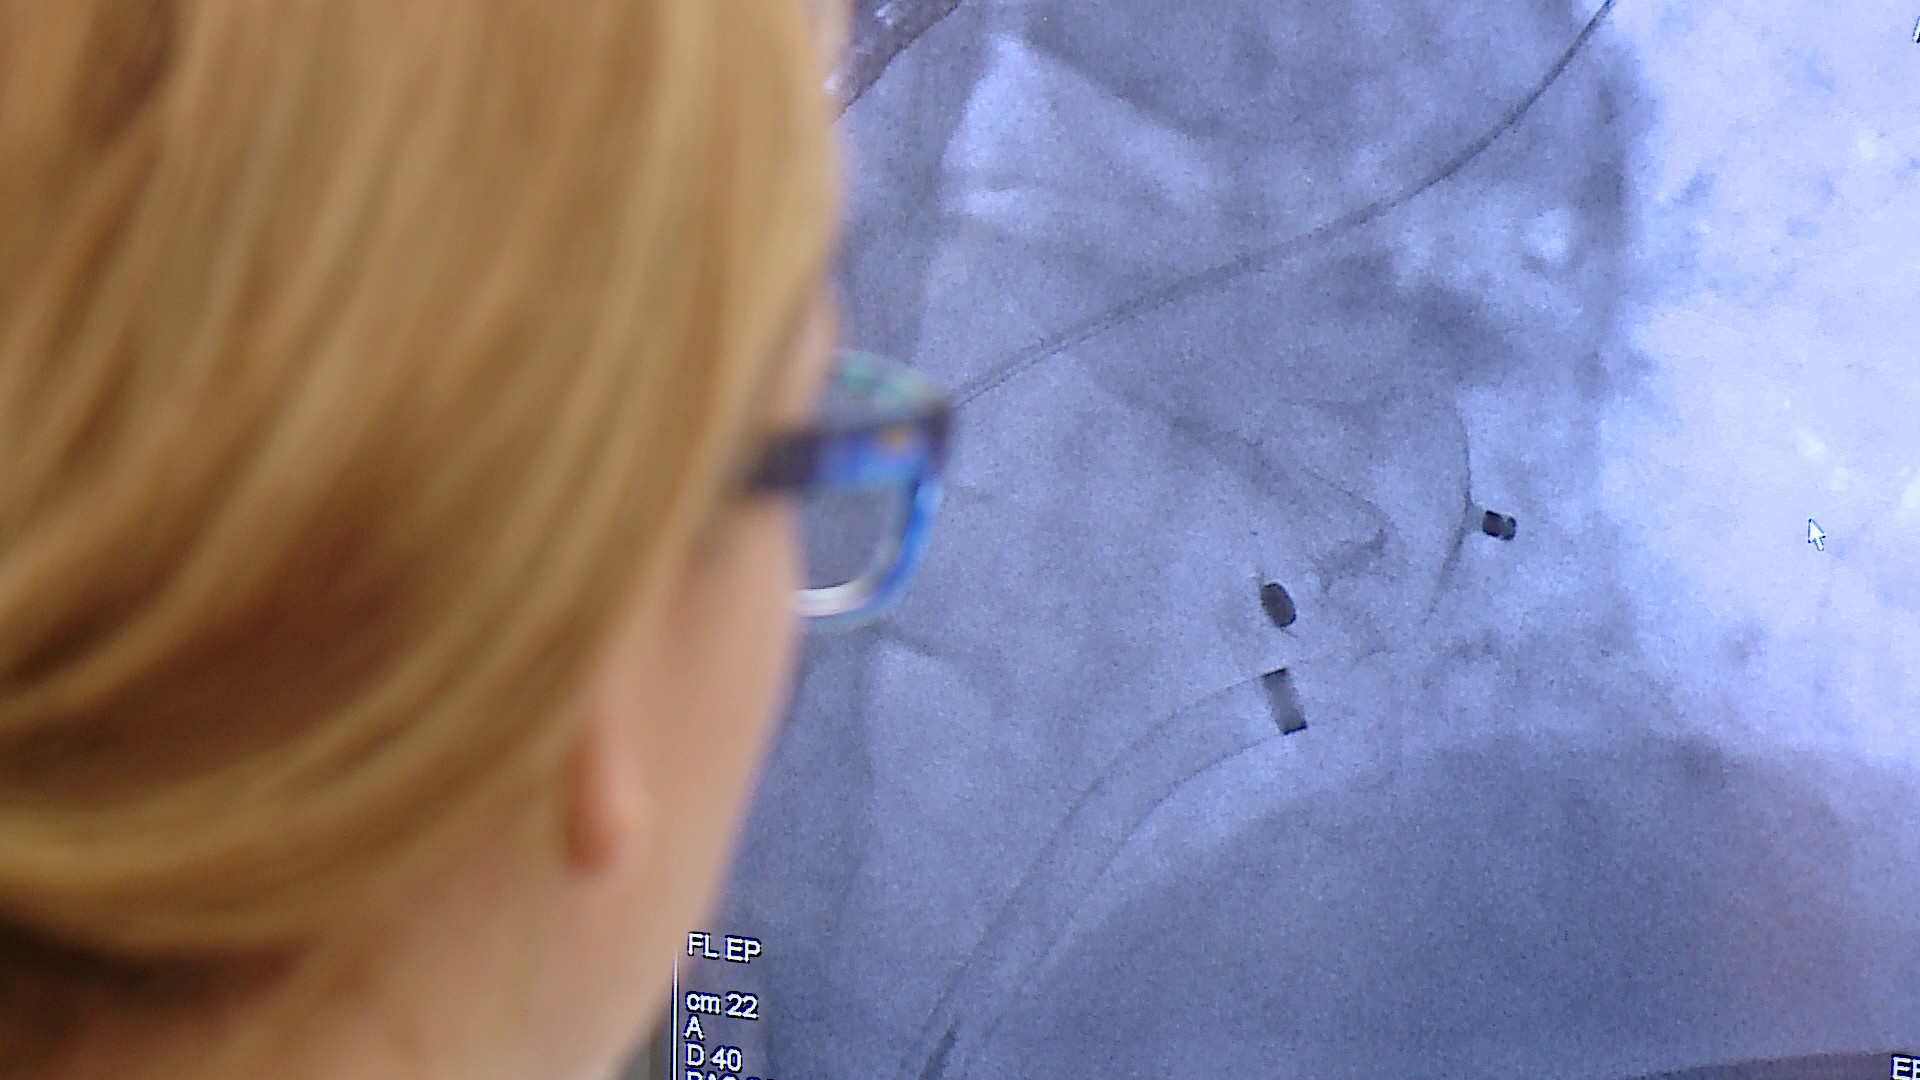

Zabieg polega na wprowadzeniu przez żyłę w pachwinie specjalnego okludera i umieszczeniu go w lewym przedsionku serca. Zabieg jest wykonywany w znieczuleniu płytkim ogólnym i trwa około godziny. Dzięki temu pacjent nie musi być hospitalizowany przez kilka dni.

Jest to zabieg korzystny dla pacjenta – podkreśla Ewa Kurek, pielęgniarka oddziałowa na kardiologii. – Pacjent po 24 godzinach trafia do domu – dodaje.

Pierwsi trzej pacjenci zostali zoperowani w poniedziałek (25 czerwca) pod okiem profesorów ze Śląskiego Centrum Chorób Serca w Zabrzu.

Wszyscy pacjenci czują się dobrze i po 24-godzinnym pobycie w szpitalu zostali wypisani do domu – mówi dr Łukasz Lewicki, kierownik Pracowni Hemodynamicznej na Oddziale Kardiologii Szpitala w Wejherowie. – Nie udałoby się to bez obecności i wsparcia zespołu kardiochirurgów, którzy od ubiegłego roku działają w naszym szpitalu. Są niezbędni, bo wykonywane przez nas zabiegi są inwazyjne i dotyczą pacjentów wysokiego ryzyka, które są obarczone ryzykiem powikłań – dodaje.